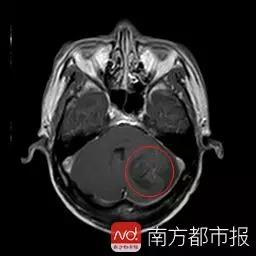

十六年来,广东湛江人刘宇(化名)饱受病痛折磨。近日,刘宇在广东三九脑科医院被诊断为脑囊虫病,医生已为其顺利切除左侧小脑半球脑囊虫占位。医生表示,患者致病可能与其食用了未煮熟的有寄生虫的猪肉有关。

今年3月,刘宇连续两周头痛剧烈,走路不平稳,遂去广东三九脑科医院就医。据该院神经外六科主任吴杰介绍,患者的影像检查提示颅内多发占位病变,结合病史,考虑为颅内多发脑囊虫病。近日,吴杰主任为患者在全麻下行“左侧小脑囊虫占位切除术”。术后病理提示为脑囊虫病。除了头部,影像检查还提示,患者双下肢也有囊虫。